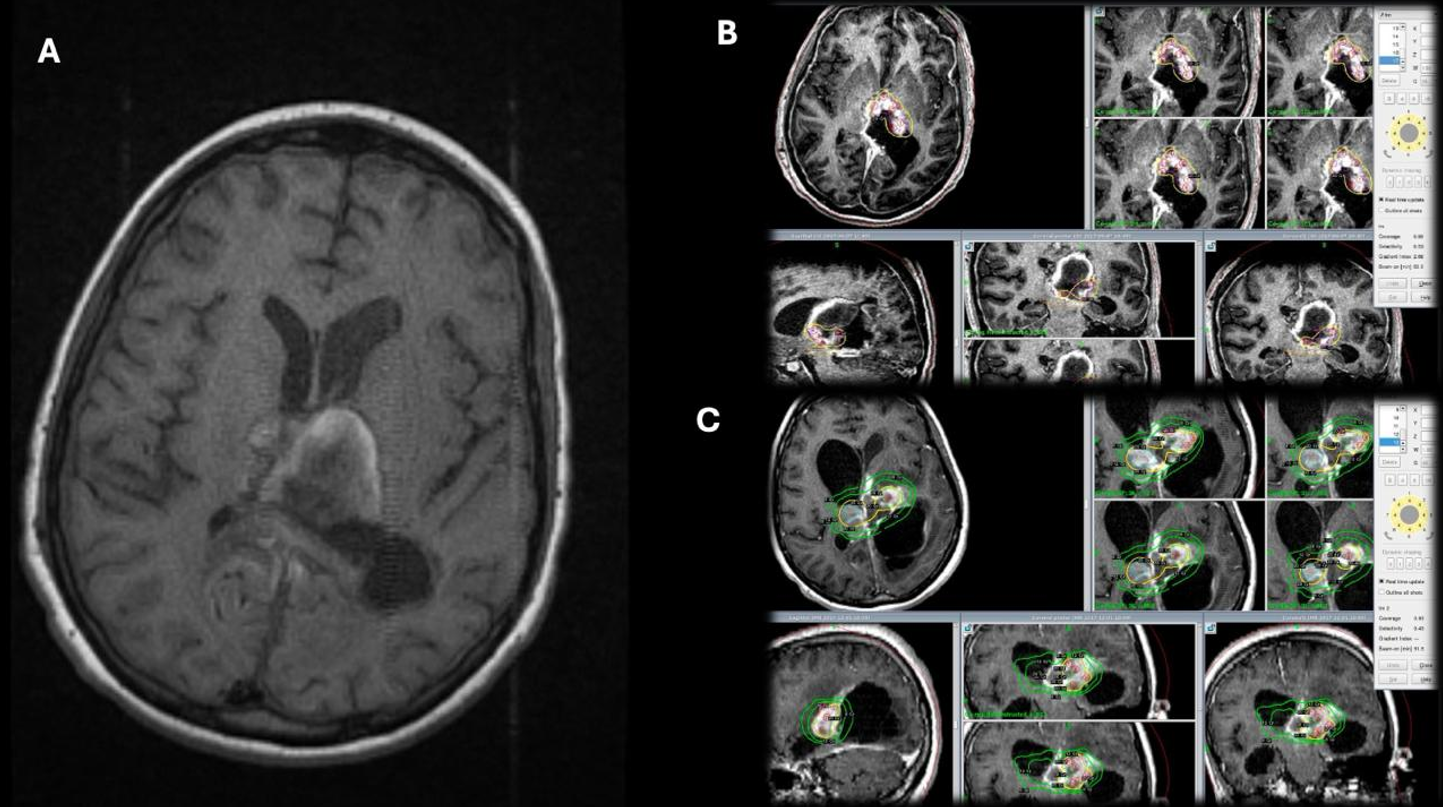

İşlem öncesinde, hastalara kontrast madde verilerek T1 ağırlıklı, ince kesitli manyetik rezonans görüntüleme (MRG) gerçekleştirildi. Ardından, hastanın yaşına uygun anestezi protokolü (1 genel anestezi, 1 sedasyon, 12 lokal anestezi) eşliğinde stereotaktik çerçeve kafatasına sabitlendi ve gerekli ölçümler yapıldı (Şekil 1). Bu işlemi takiben bilgisayarlı Beyin tomografisi (BBT) çekildi. Elde edilen MRG ve BBT verileri bilgisayar ortamında birleştirilerek, tedavi planlama yazılımı aracılığıyla lezyona özgü radyasyon dozu belirlenerek uygun tedavi planı oluşturuldu (Leksell Gamma Knife® Perfexion™, Elekta). GKRC uygulamasının tamamlanmasının ardından çerçeve çıkarıldı ve hastalar yaklaşık 1 saat klinik gözlem altında tutuldu. Herhangi bir komplikasyon ya da ek semptom gelişmeyen olgular, aynı gün taburcu edildi.

Patolojik tanılara göre değerlendirildiğinde en sık karşılaşılan tümör grubu gliyal tümörler olup, dört hastada saptanmıştır. Bu hastaların ilki 15 yaşındaki kız hasta patoloji sonucu DSÖ derece 3 gliyal kitle olarak raporlanmıştır. Cerrahi sonrası dönemde rezidü kitlesine yönelik lezyon için Karnofsky skoru düşük olması nedeniyle radyoterapi (RT) uygun görülmedi ve hastaya GKRC yapıldı. 5. ay kontrol görüntülemesinde lezyon boyutlarında artış olması ve Karnofsky skoru düzelen hastaya RT yapıldı. Hasta RT’den 2 ay sonra vefat etti. İkinci hasta 15 yaş kız hasta olup patolojisi yüksek dereceli gliyal kitle olarak sonuçlanmış. Karnofsky skoru düşük olduğu için hastaya RT yapılamadı ve GKRC planlandı. 7. ay kontrol görüntülemesinde progresyon izlenen hastanın Karnofsky skor düşüklüğü olması nedeniyle RT planlanmadı ve tekrar GKRC uygulandı. Hasta ilk GKRC tedavisinin 8. ayında vefat etti (Şekil 2). Diğer iki olgudan biri olan 17 yaşındaki kız hastada beyin sapı yerleşimli pilositik astrositoma (DSÖ Derece 1) yönelik hacim bölünerek 18 aylık süreçte 5 farklı seansta ve her tedavide stereotaktik çerçeve yeniden uygulanarak GKRC gerçekleştirildi. 96 ay sonunda lezyonda küçülme izlendi. Bu olguda lezyonun hacmi ve beyin sapı yerleşimi nedeniyle kritik nörovasküler yapılara yakınlığı göz önünde bulundurularak hacimsel evreleme uygulanmış, hedef hacim alt bölümlere ayrılarak farklı marjinal dozlar her bir alt hacme ayrı ayrı planlanmış ve belirli zaman aralıklarıyla uygulanmıştır. 11 yaşındaki erkek hastada ise tektal yerleşimli Diffüz Astrositomun (DSÖ Derece 2) tedavi sonrasındaki 96 aylık takibinde stabil seyrettiği görüldü. Patolojilere göre marjinal doz, takip süreleri ve sonuçlar Tablo 1’de özetlenmiştir.